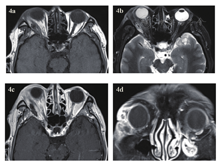

急诊入院者16例,均行眼眶CT检查,其中6例患者发现异物影(37.5%),发现异物影者主要为铅笔或筷子类异物(图1a、b),而竹子类异物较难发现,多表现为絮状密度影等感染征象、不能显示明显异物影(图1c、d);早期入院者7例,均行眼眶CT检查,其中4例发现异物影(57.1%),表现为条状或片状低密度影,周围伴软组织密度影(图2);中晚期入院者19例,4例在外院行了眼眶CT外余均在我院行眼眶CT检查,其中16例扫描表现为高密度条索状或片状异物影(84.2%),大部分能显出异物大致轮廓,周围多伴有软组织密度影(图3)。